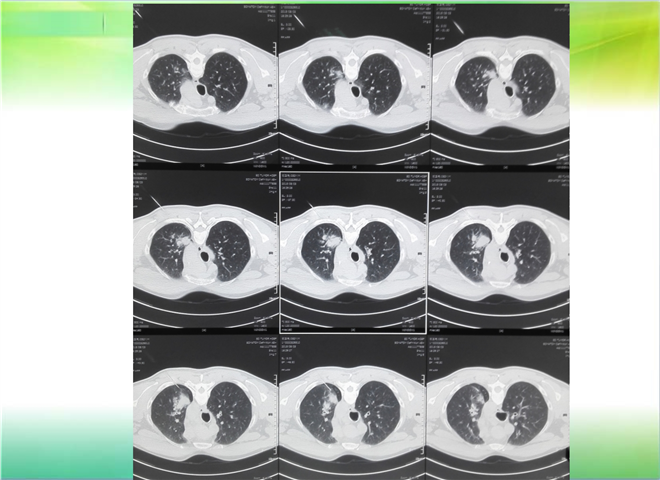

CT引导下穿刺活检术